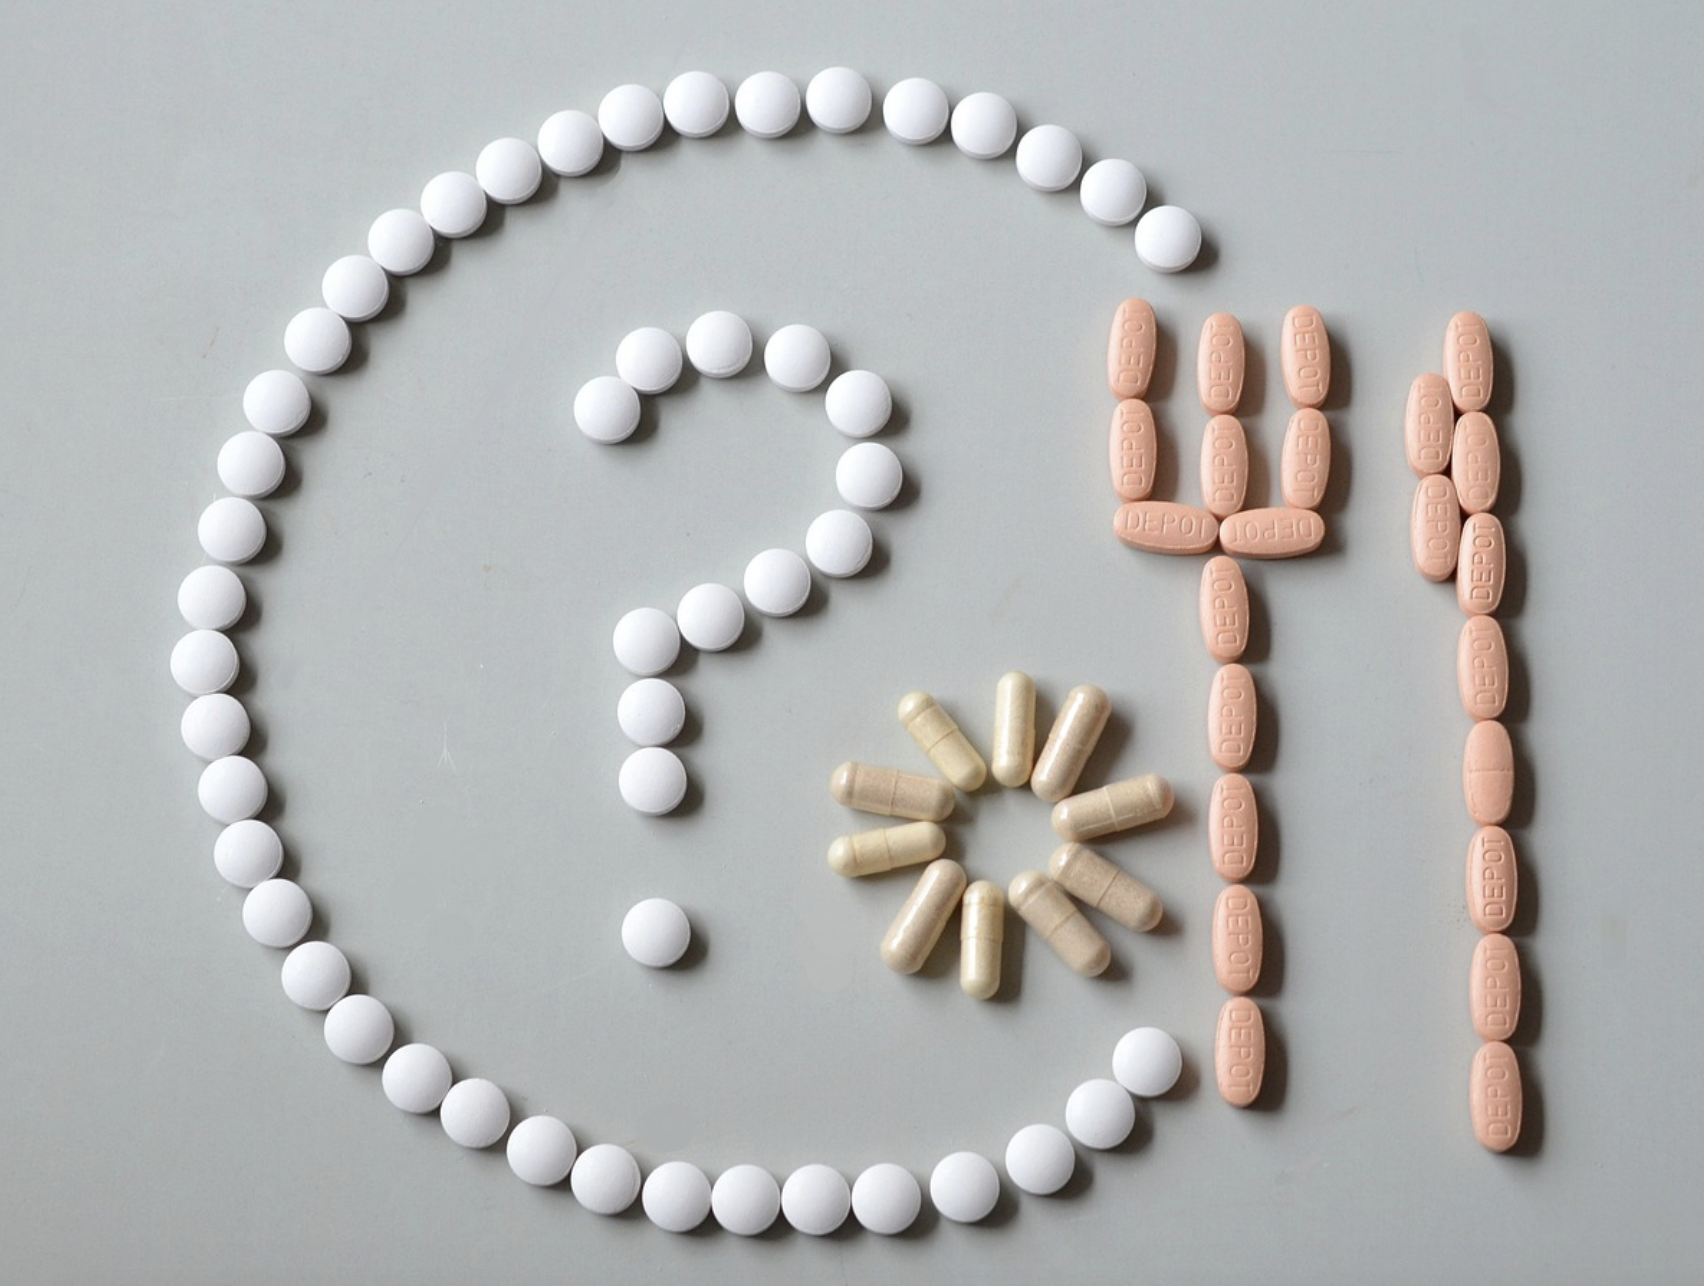

뇌경색 치료법

급성 뇌경색 치료 시기를 놓친 환자들은 합병증 발생을 막기 위해서 보존적 치료와 함께 항응고제를 투여해서 재발을 억제하는 치료를 해야 합니다. 그래야만 장기적으로 뇌의 역할을 발휘할 수 있게 되는데요. 만성인 경우에는 재발하지 않도록 재활치료를 꾸준히 해야합니다.

뇌경색을 예방하기 위해서는 평소 식습관이나 생활습관이 중요한데요. 흡연이나 음주는 피해야 하고, 자신이 심장병 환자, 당뇨 환자, 고혈압 환자라면 조금 더 주의하셔서 식사를 하셔야 합니다. 적절한 운동은 필수이고, 혈관에 좋은 음식들을 위주로 식단을 짜야합니다. 뇌경색은 손상의 위치에 따라서 수일 이내로 회복이 가능하기도 하지만, 손상이 크거나 중요한 부분이 손상된 경우에는 수년에 걸쳐서 느리게 회복되거나 회복되지 못하는 경우도 있는데요.